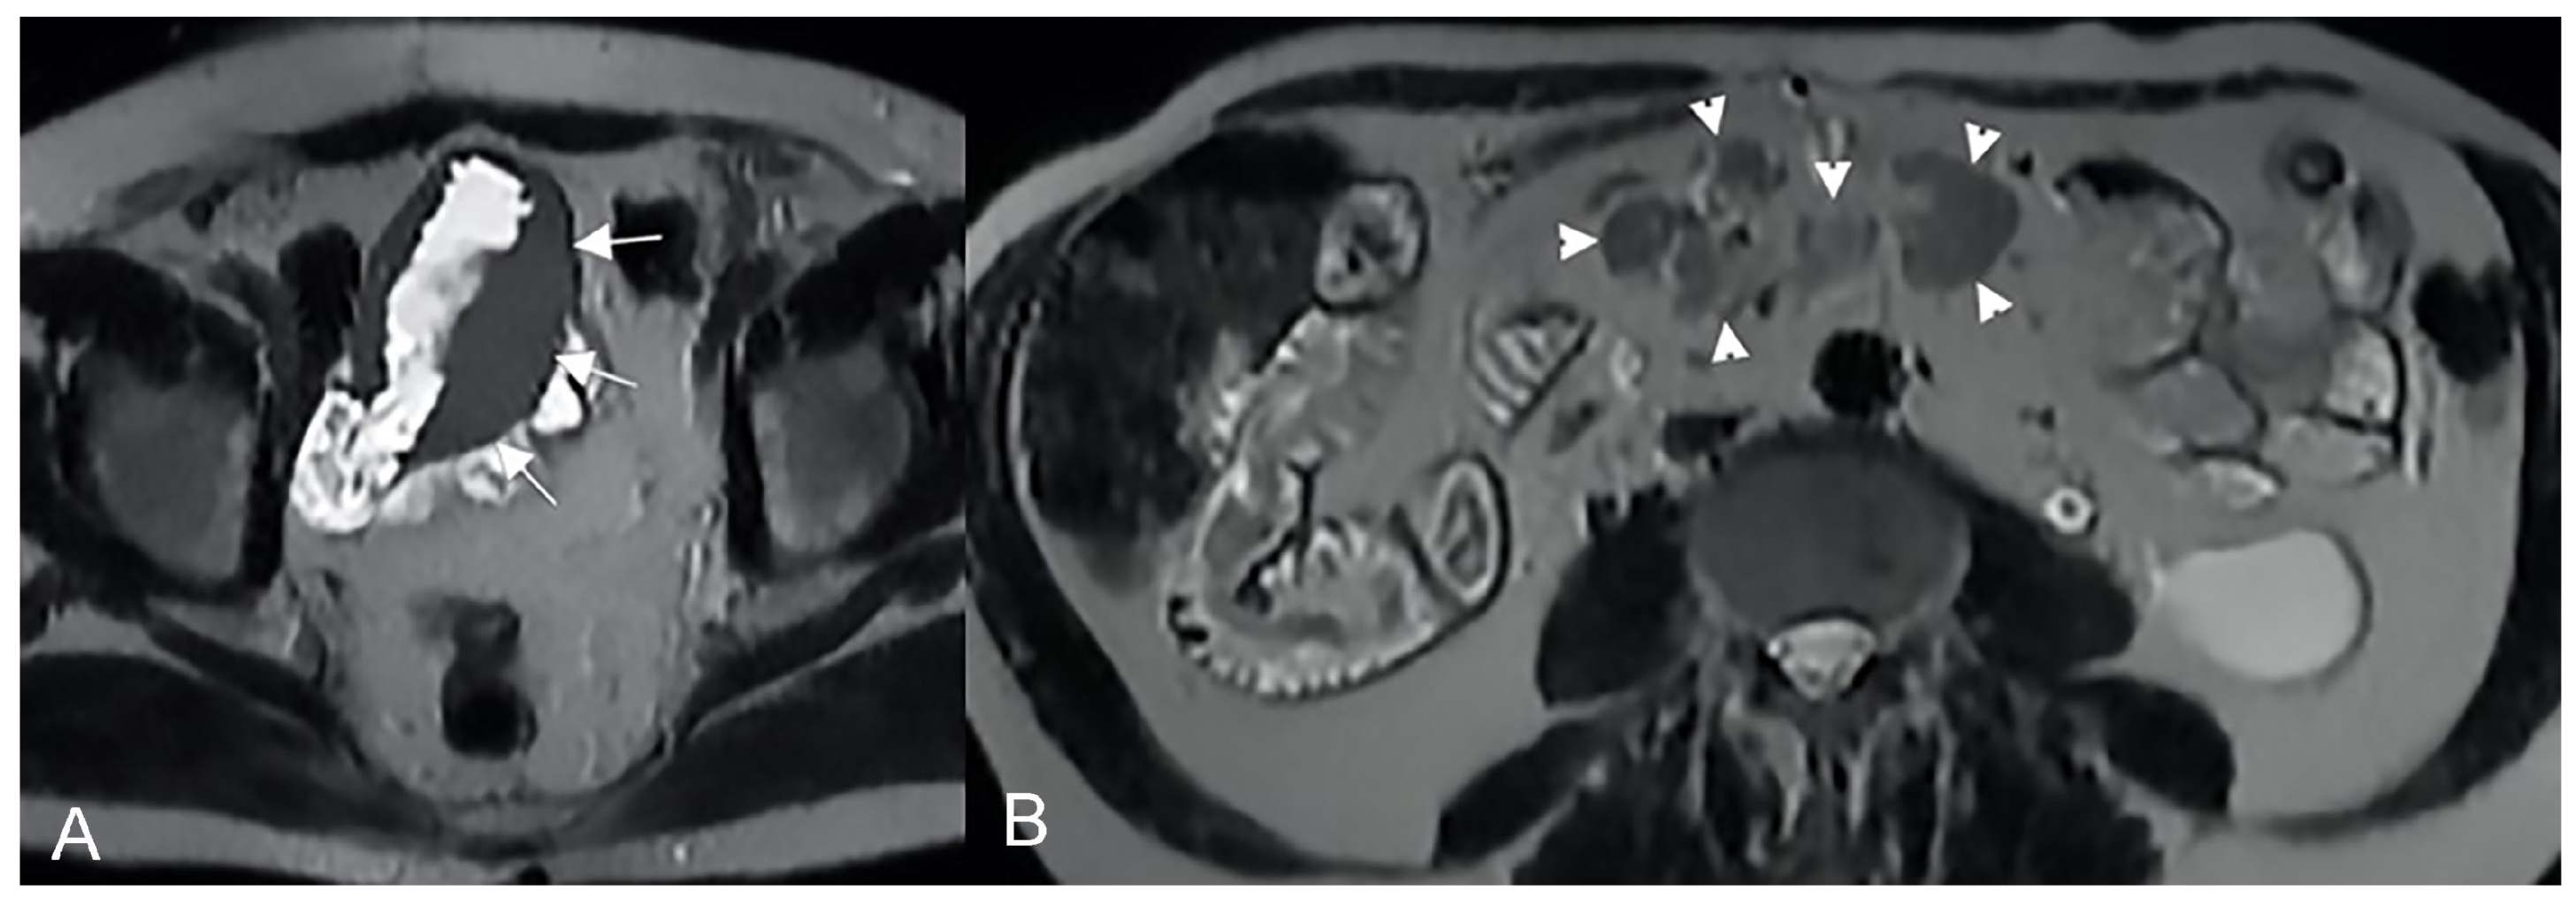

The infiltrative pattern is characterized by circumferential involvement of the wall, and it is responsible for different degrees of wall thickening and disappearing of the normal wall layers. Bowel wall infiltration looks like segmental and circumferential thickening, with homogeneous enhancement after gadolinium injection [33,34] (Figure 22).

Figure 22.

Example of Lymphoma in a 71-year-old male patient (the same patient in Figure 1C). (A) Axial T2-weighted image shows a marked asymmetric thickening of an ileal loop in the pelvis (arrows). (B) An axial T2-weighted image on a different plane shows multiple enlarged mesenteric lymph nodes (arrowheads).

The aneurysmal pattern often coexists with the infiltrative one and it can be its evolution. In this pattern, lymphomatous infiltration and disruption of the muscle layer and neural plexuses may be appreciated, resulting in loss of muscle tone and consequent bowel dilatation.

Regarding the differential diagnosis, an aggressive adenocarcinoma with ulcerations should be considered.

MRI is suggestive for lymphoma when a bowel wall aneurysmal mass without proximal bowel occlusion is seen. The diagnosis can be supported by splenomegaly and retroperitoneal and mesenteric enlarged lymph nodes. Adenocarcinoma is characterized by the invasion of the surrounding mesenteric folds (less for lymphoma), while mesenteric ill-defined confluent masses enveloping the bowel are more frequent in lymphomas [33].